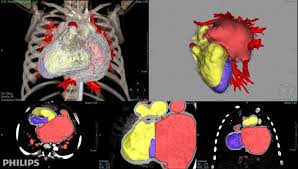

IntelliSpace Portal

IntelliSpacePortalEnterprise

One work environment, one solution

A single advanced visualization solution connecting multiple locations.